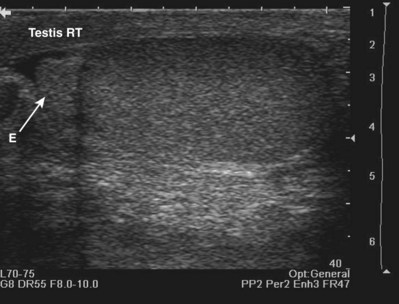

By convention, structures imaged by ultrasonography should be oriented so that the superior aspect of the structure is to the left as the image is viewed and the inferior aspect of the structure to the right. With paired structures it is critically important to document right or left. It is useful to use equipment-generated icons to illustrate patient position and the orientation of insonation (Fig. 4–30).

Figure 4–30 In this sagittal image of the right testis, the superior pole of the testis (A) is to the left, the inferior pole of the testis (B) is to the right. The anterior aspect of the testis (C) is at the top of the image and the posterior aspect (D) at the bottom. Without the label, there would be no way to distinguish the right from the left testis.